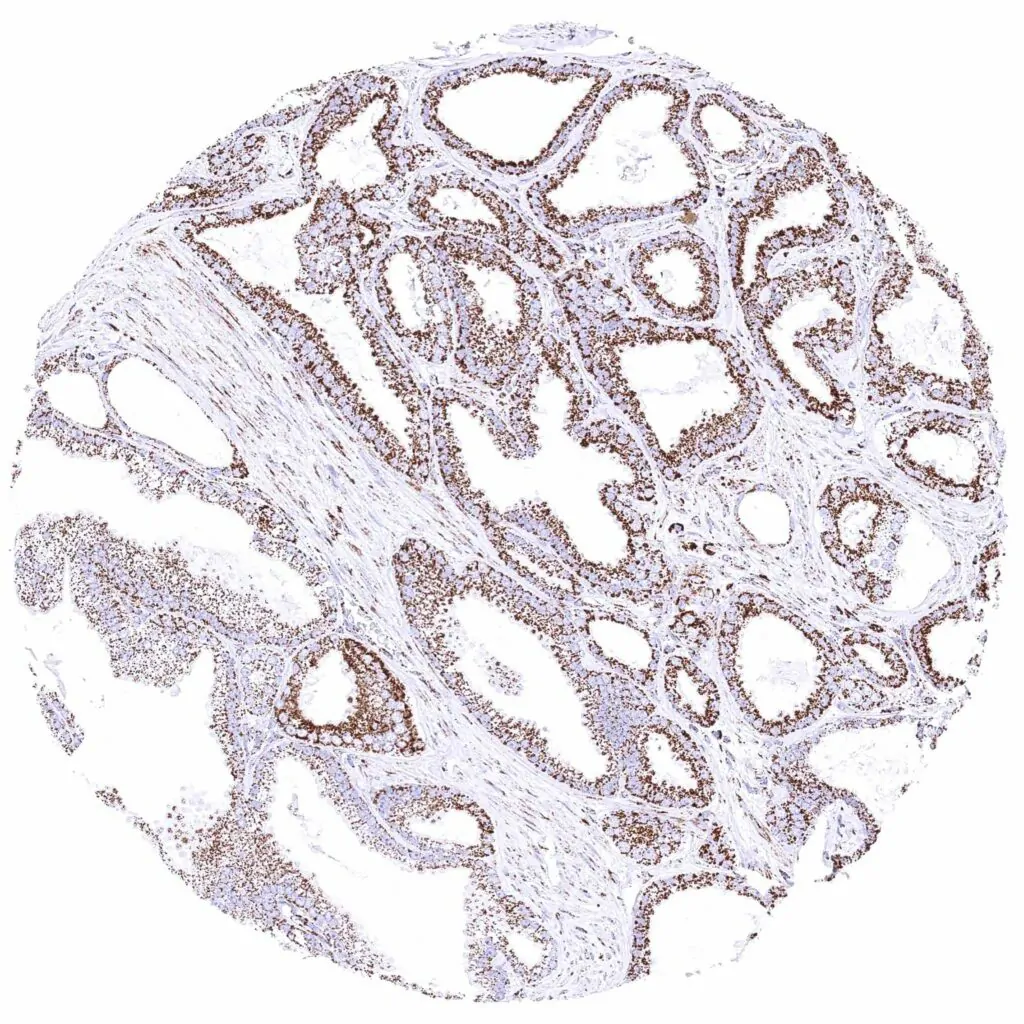

Prostate – Adenocarcinoma (Gleason 3+3=6) with moderate cytoplasmic ATP5J staining of tumor cells.